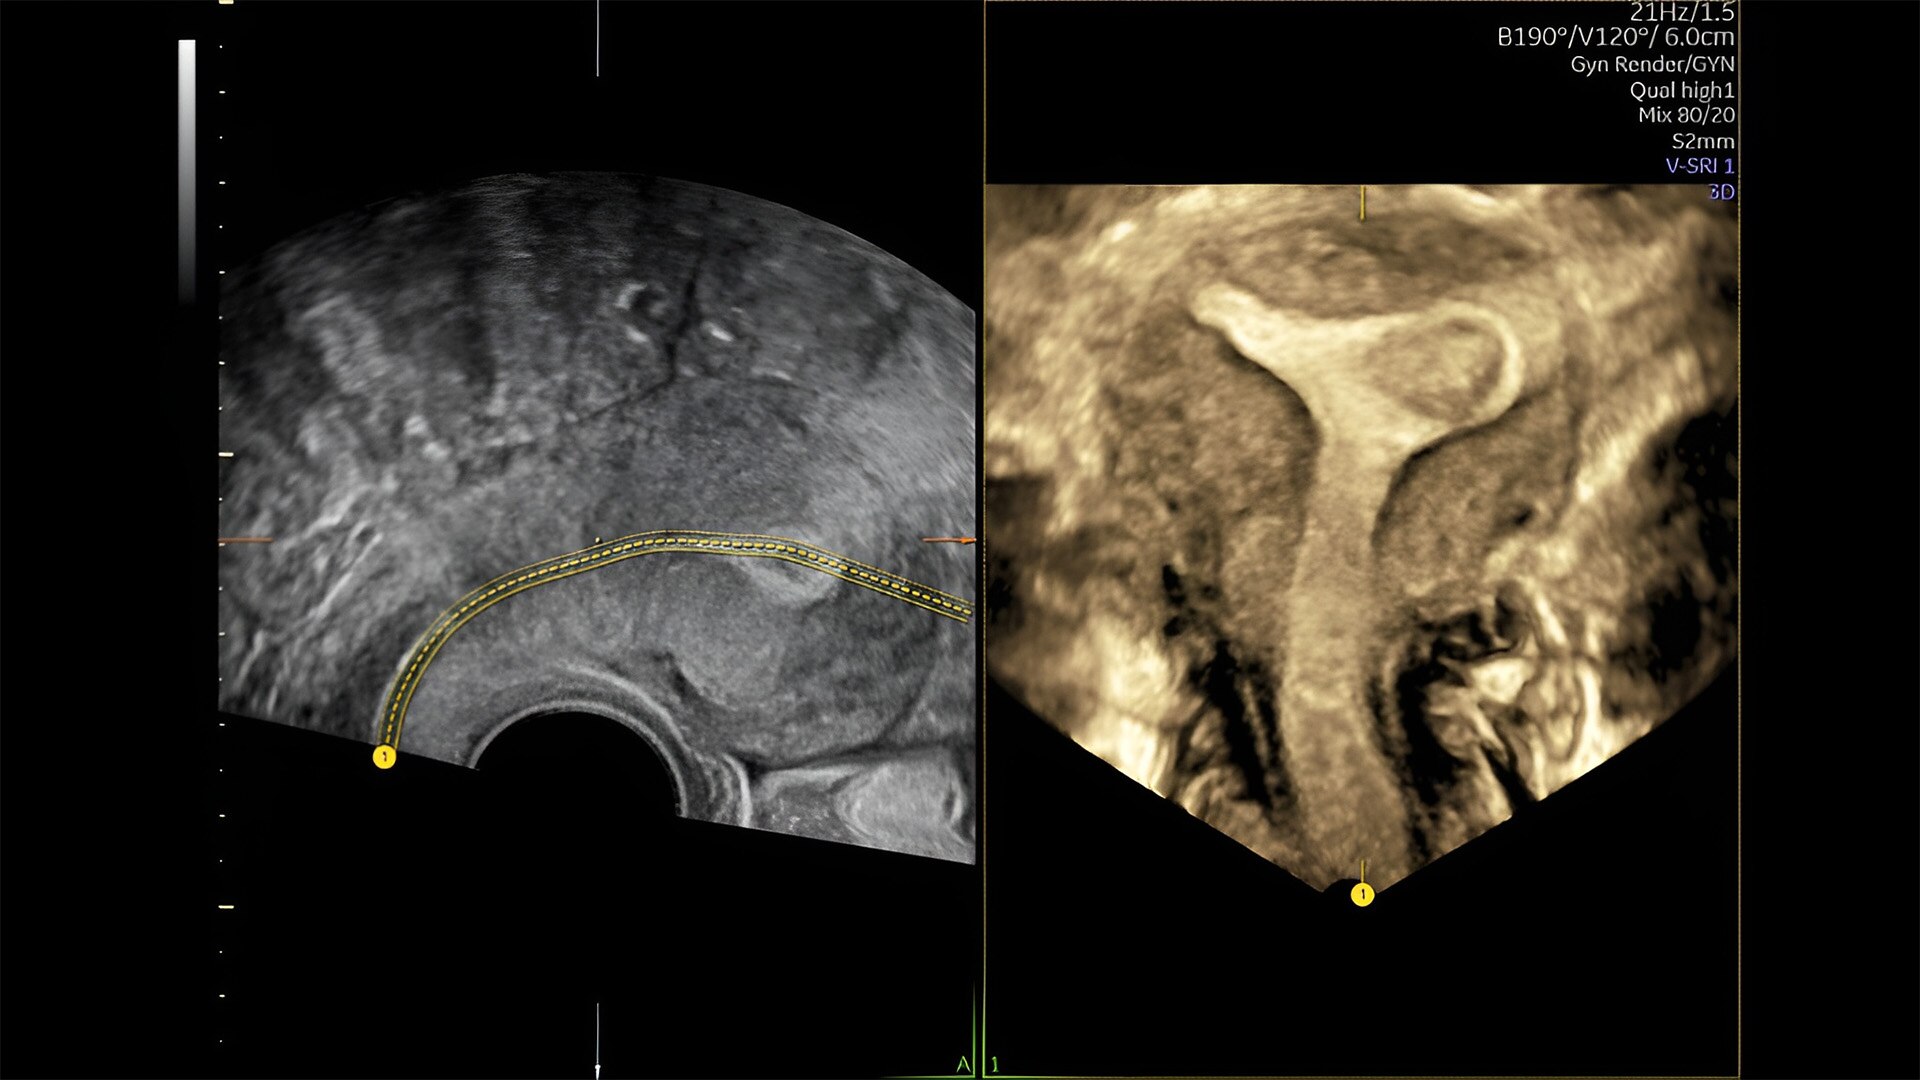

Pelvic health

Offer patient answers faster with Ai-based automation tools